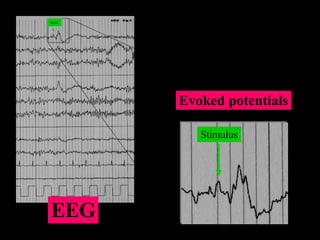

¿Qué es un Potencial Evocado? Desde otro punto de vista, los Potenciales Evocados son registros de la actividad eléctrica del cerebro, en respuesta a un estímulo especifico que puede ser de índole auditiva, somatosensorial o visual. Se presentan como oscilaciones enmascaradas por la señal de ElectroEncefaloGrafía (EEG) y se describen, por lo general, en términos de sus magnitudes máximas y mínimas (amplitudes pico) y de su duración relativa respecto al estímulo (latencia).

Registro de Potenciales Evocados Las amplitudes de los PEs van de las décimas de microvolt a decenas de microvolts, (1-40) y, por convención, las amplitudes positivas se consideran negativas y viceversa. De acuerdo a esta convención y considerando la latencia, las amplitudes características se designan como N1 (N100), P1 (P100), P3 (P300), etc. Estas amplitudes juegan un papel muy importante en el análisis de los PEs

Stim Stimulus EEG Evoked potentials

Stim Stimulus EEGEvoked potentials